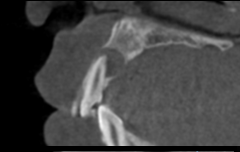

上唇の腫脹を認め、CT検査にて根尖部に嚢胞様透過像を認めた。左上の前歯が不自然に大きく噛み合わせが強くなっていたことがフレアアップの一因と考える。精密根管治療を行い、感染経路を遮断したのち歯根端切除術にて嚢胞を摘出した。

治療前